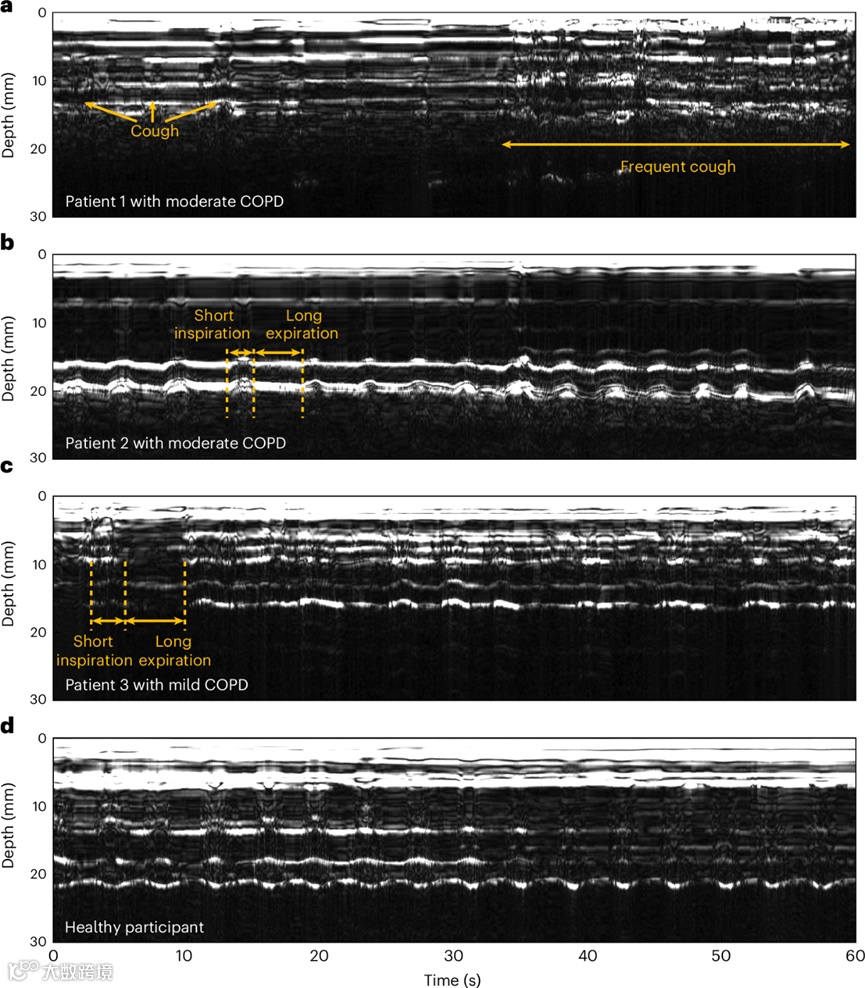

COPD 患者的膈肌监测

招募了三名慢性阻塞性肺病(COPD)患者,他们的肺气道发炎、变窄,并在呼气期趋于塌陷。在这种情况下,身体通过咳嗽迫使空气通过气道。此外,呼吸的呼气阶段通常会延长。患者1的呼吸相对较浅,咳嗽频繁,导致单传感器采集的M模式图像中隔膜轻微移动。由于咳嗽是主要症状,M型图像显示频繁波动。患者2有非常典型的吸气时间短和呼气时间长的症状。由于患者3患有轻度慢性阻塞性肺病,症状轻微,M模式图像显示吸气和呼气都有规律,只有偶尔长时间呼气。在健康的参与者中,吸气期和呼气期相对一致。这些结果表明,单个传感器可以区分健康参与者和慢性阻塞性肺疾病患者的呼吸模式,显示出其临床潜力。

图4. COPD 患者和健康参与者的隔膜监测